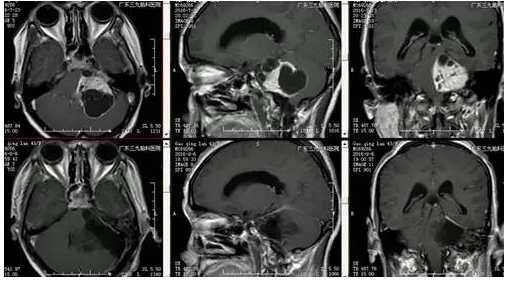

高女士,43岁,头痛伴行走不稳,伴轻度面瘫1月余入院,行颅脑CT及MR示颅内占位肿物51.4mm×38.6mm×40.4mm,其内可见大小不等囊变,增强后囊壁及肿块实质部分可见明显强化,肿块与左侧内听道关系密切,左侧内听道扩大,脑干受压右移,诊断:左侧桥小脑脚区占位性病变。

因肿瘤体积大,术中对面听等后组神经的保护也更为困难,据统计数据显示直径大于4cm的神经鞘瘤,其面听神经保留率在75%以下,所以,术中保护患者现有神经功能成了一个挑战。手术由神经外一科张良主任主刀完成,在全麻下行左侧桥小脑脚区占位性病变切除术,术中采用神经电生理监测,有效预防面神经和听神经的损伤,术后患者病情平稳,面瘫症状未有明显加重,听力未受影响。经术后系统的药物治疗和康复理疗后,患者康复出院。病理提示:神经鞘瘤。